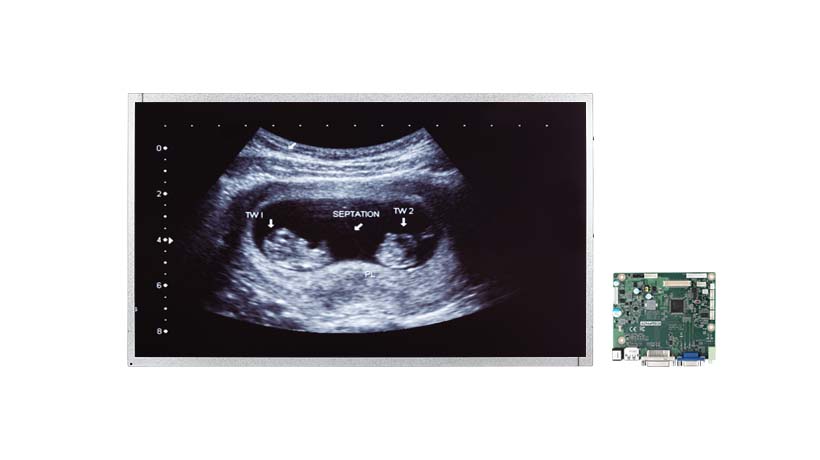

IDK-1121MD21.5英寸FHD 医疗显示套件,带灰度调节AD板...查看产品

IDK-1121MD21.5英寸FHD 医疗显示套件,带灰度调节AD板...查看产品 -